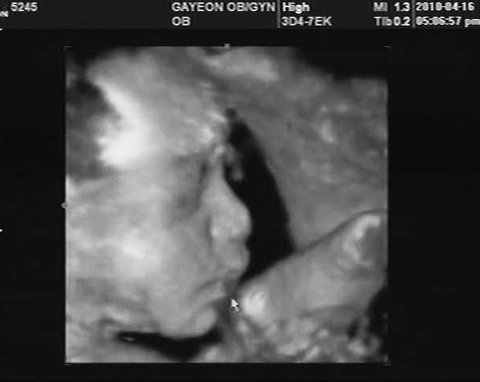

[ 임신 27주 마오 모습 ]

세상에..

이제는 정말 바로 앞에서 너와 눈마주치는 기분이 들만큼 ..

그렇게 보삭보삭 부둥부둥해진 너의 얼굴  ㅠ.ㅠ

이마며, 눈이며, 코며, 인중이며, 입술이며 . .

한 시간 전에 했던 엄마의 요가처럼

너 또한 비수무리 흉내내고 있는 양 발꿈치와 맞닿아 있는 새초롬 입술이

어찌나 앙증스럽게 귀엽던지.

나도 모르게 눈물 그렁그렁 돌아

" 어쩜.. 너 너무 귀엽게 자랐다 " 말하는 엄마를 향해

눈을 찡긋찡긋 해주던 마오.

2010. 04  가연산부인과 , photographer  Choiyuri